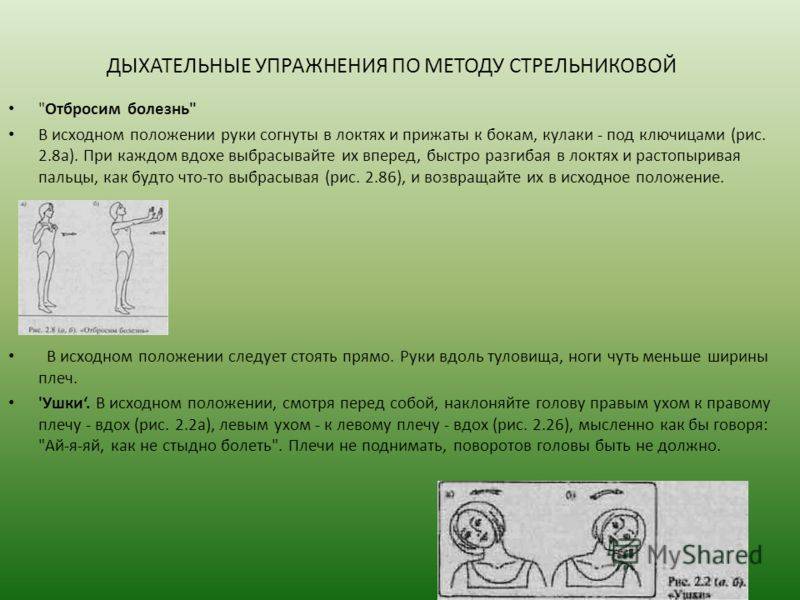

Дыхательная гимнастика при пневмосклерозе: техника и советы

Раздел: Визуальные уроки